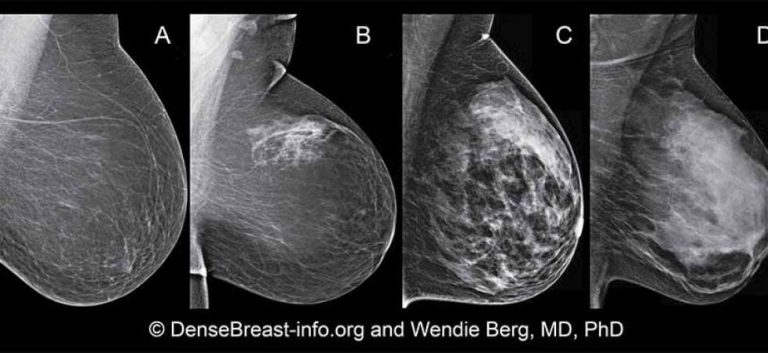

La densità della mammella è correlata alla quantità di ghiandola presente. É una caratteristica biologica costituzionale che però ha degli effetti importanti sulla salute della donna. Avere più ghiandola vuol dire avere un rischio aumentato di sviluppare un cancro mammario. Purtroppo, vuol dire anche correre il rischio di ritardi nella diagnosi. Ciò dipende dal fatto che l'esame cardine dello screening senologico, la mammografia, perde parte della sua capacità diagnostica (dal 90 al 60%) perché sulla immagine radiologica il parenchima ghiandolare appare radioopaco ("bianco sulla lastra scura") nascondendo eventuali carcinomi che appaiono anch'essi radiopachi. Spesso in questi casi il referto rilasciato descrive una alta densità con la sigla ACR=D e assegna come classe di rischio BIRADS 0. Ma attenzione, ciò non vuol dire che non c'è alcun rischio, ma che l'esame non è in grado di valutare la presenza o meno di tumori, ovvero risulta inconclusivo!

Quindi attenzione a far leggere sempre gli esami strumentali al proprio medico o al proprio senologo. Indirizzare le donne con seno denso ad approfondimento con ecografia mammaria ed eventualmente RM mammaria bilaterale con e senza mdc può essere decisivo! E tu che seno hai? Vai a leggere il tuo referto mammografico o fai mammografia se hai più di 40 anni e non l'hai ancora eseguita!